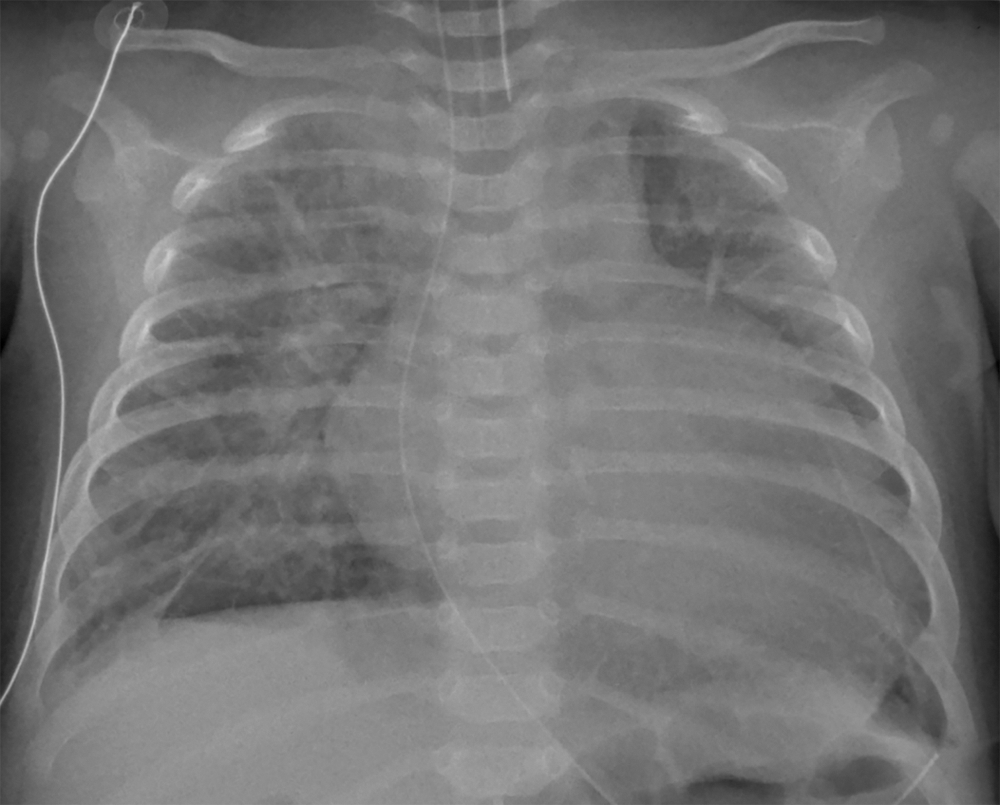

Chest X-ray (Fig. 1) demonstrated cardiomegaly with pulmonary edema. The electrocardiogram demonstrated T wave inversion in the left lateral leads. Troponin I was 0.48 ug/L (normal high <0.05) and BNP was >5000 ng/L (normal high <37). Echocardiography revealed severe left ventricular dysfunction from qualitative and quantitative assessment with an ejection fraction of 12%, with a dilated left ventricle (LVd z-score +5) and a right aortic arch. Echo imaging of the arch was challenging, however, there was evidence of right arch coarctation on the two-dimensional images and a mild diastolic tail on Doppler interrogation. There was a left sided vessel supplying the descending aorta with laminar flow. Despite these findings, there was no upper/lower limb blood pressure gradient and there was no brachiofemoral difference in palpation of the peripheral pulses. An estimate of the LV systolic pressure, obtained from the mitral regurgitation Doppler jet, when compared to a non-invasive peripheral systolic blood pressure, demonstrated a pressure difference of 50 mmHg between the LV and the peripheral blood pressure measured in the extremities.

Figure 1: Chest X-ray on admission. Cardiomegaly with marked pulmonary interstitial edema and right basal linear atelectasis